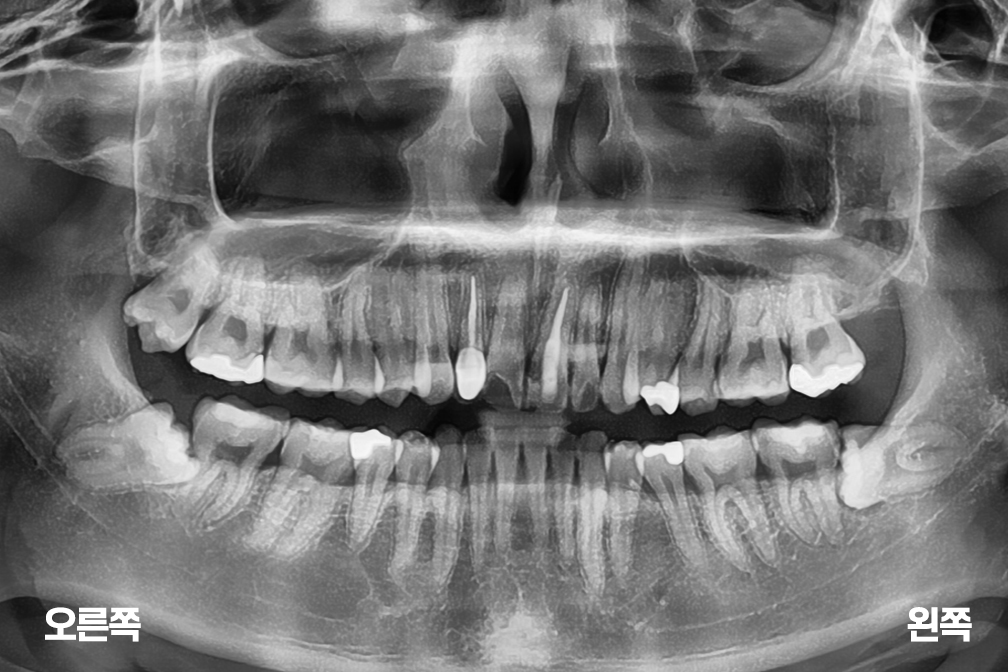

사랑니발치 사랑니 3개 발치

사랑니 발치